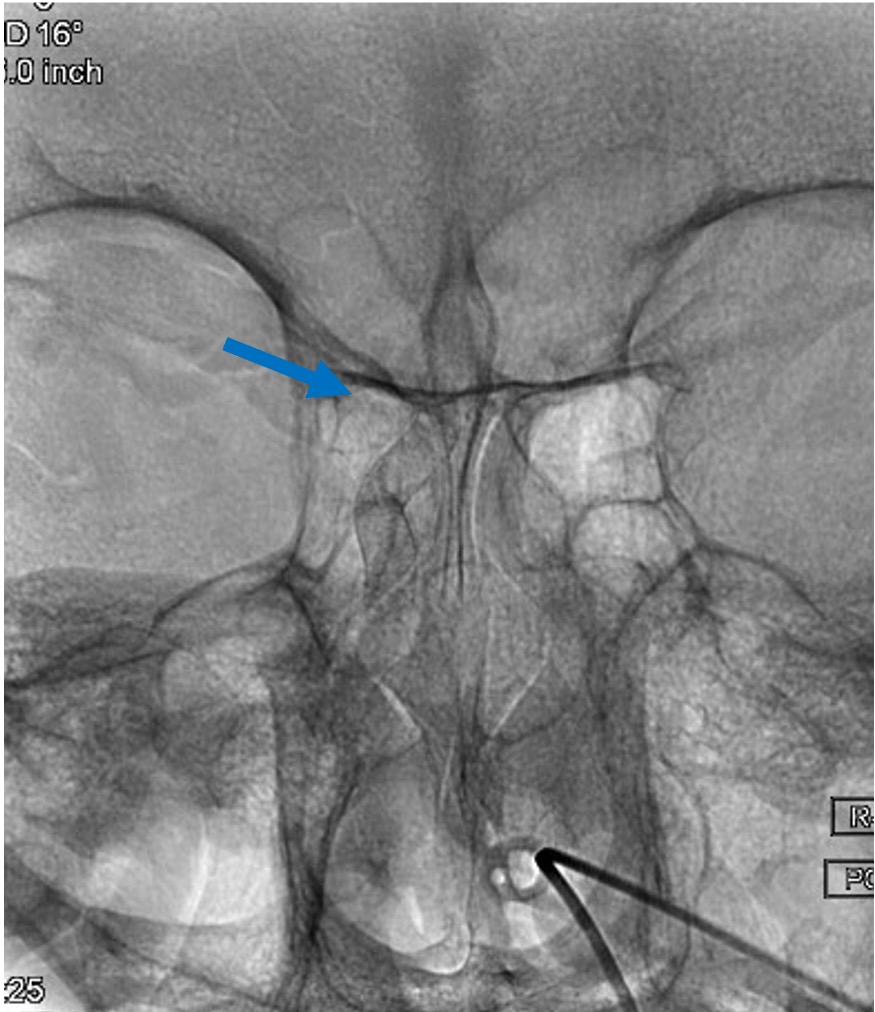

その1例を提示します。患者さんは65歳女性です。頭痛でMRIAを行い、血管撮影にて図1赤矢印の様に最大径7.8mm.ネック径4mmで、パイプラインというフローダイバーターステント(X線にて確認可能、図2〜5青矢印)を留置しました。その後、4ヶ月後の血管撮影ですが、図6緑矢印の様に動脈瘤は消失しています。